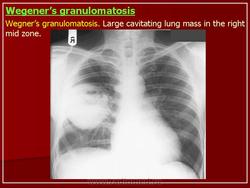

Поражение легкихразвивается у 3/4 больных, проявляется формированием инфильтратов, которые могут распадаться и образовывать полости. Иногда наблюдается плеврит.

При генерализованной форме ........ картина пневмонии с наклонностью к абсцедированию и появлению плеврального выпота.

Рентгенологическое исследование легких: инфильтраты, часто с распадом и образованием полостей, редко - плеврит.